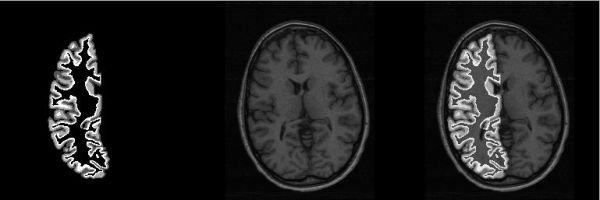

Figure 1 shows a cross-section of the resulting cortical mantle volume imposed on an MRI slice. We are using these masks to restrict fMRI analysis to the cortical mantle. FSL [2] is being used to perform GLM analysis on a block design parametric static force BOLD fMRI dataset [3] of the 16 subjects. The SPMs from two single runs for each subject are masked by the cortical mantle mask. Correlation between the two SPMs generated for each single run are computed using the unmasked SPMs and also using the cortical mantle masked SPMs.